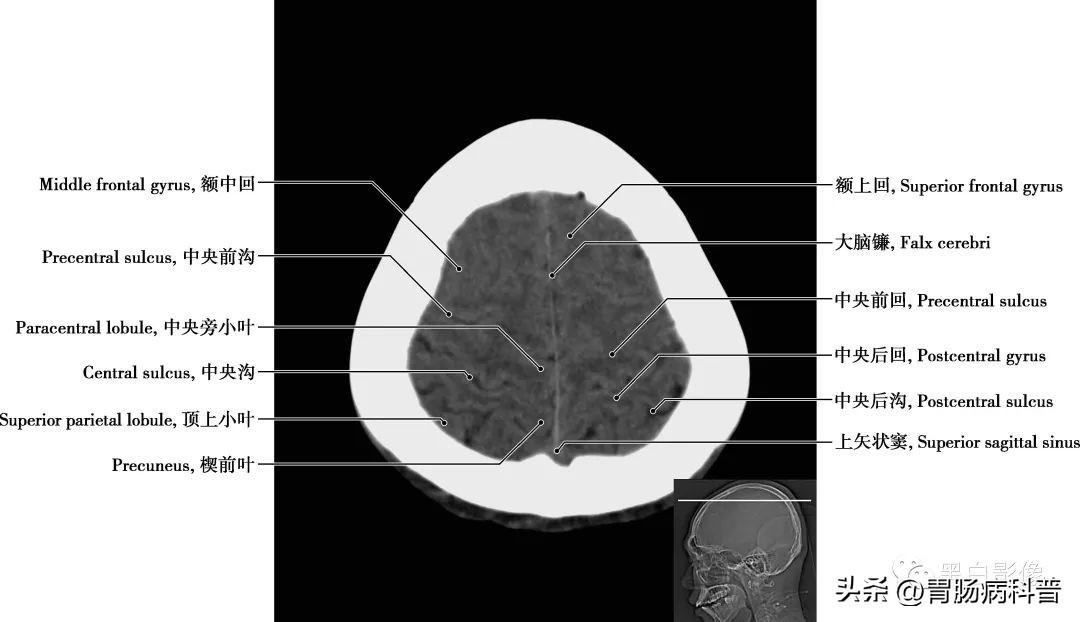

图1-1-3 经中央旁小叶上部轴位切面

中央沟 起于半球中点稍后方,斜向前下方,下端与外侧沟隔一脑回,上端延伸至半球内侧面,是额叶与顶叶的分界线。大脑镰 由硬脑膜形成,呈正中矢状位,前窄后宽,似镰刀状,分隔左、右大脑半球;其上、下缘分别有上矢状窦和下矢状窦,前下缘附着于鸡冠,后下缘与小脑幕相连,连接处形成直窦